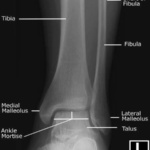

Las radiografías, generalmente llamadas rayos X, producen imágenes como sombras de huesos y ciertos órganos y tejidos. Las radiografías son muy buenas para detectar problemas óseos. Pueden mostrar algunos órganos y tejidos blandos; sin embargo, la MRI y la CT suelen crear mejores imágenes de los mismos. Aun así, las radiografías son rápidas, fáciles de obtener y menos costosas que los otros estudios, por lo que se pueden usar para obtener información rápidamente.

Un tubo especial dentro de la máquina de rayos X emite un haz de radiación controlada. Los tejidos del cuerpo absorben o bloquean la radiación en diferentes grados. Los tejidos densos como los huesos bloquean la mayor parte de la radiación, pero los tejidos blandos, como la grasa o los músculos, bloquean menos radiación. Después de pasar por el cuerpo, el haz alcanza una pieza de un fragmento de película o un detector especial. Los tejidos que bloquean altas cantidades de radiación, como los huesos, aparecen como áreas blancas en un fondo negro. Los tejidos blandos bloquean menos radiación y aparecen en tonos de gris. Los órganos que contienen principalmente aire (como los pulmones) aparecen en negro. Los tumores son por lo general más densos que el tejido que los rodea, por lo que suelen verse en tonos grises más claros.